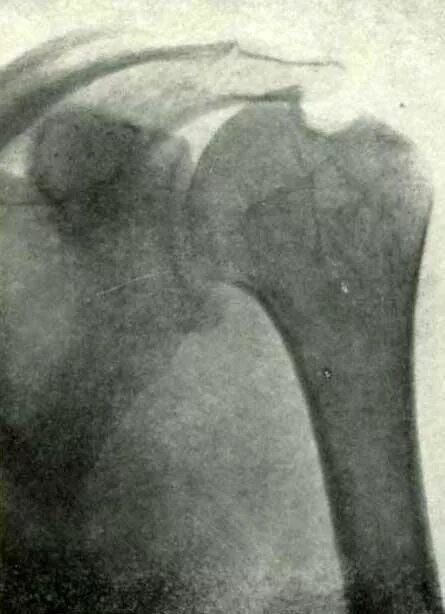

Туберкулез суставов симптомы